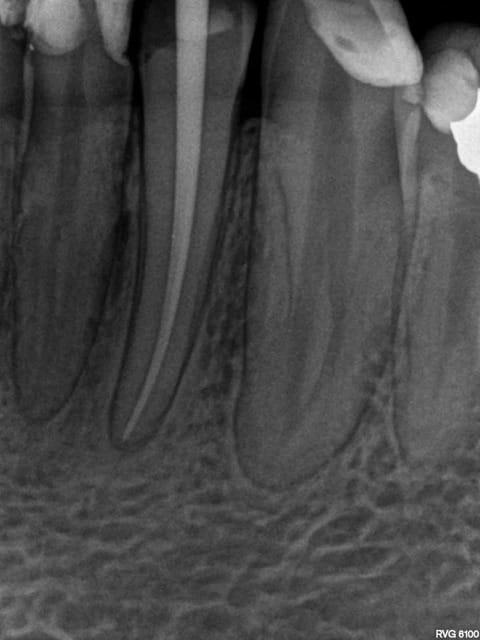

Mais on a tendance a faire plus de dépassements quand meme !

1 gecyy2 - Eugenol

2 hbvai8 - Eugenol

3 kk4a4s - Eugenol

Mais des fois pas; -))))

4 e2a0sa - Eugenol

5 aeh0p3 - Eugenol

6 pby5bu - Eugenol